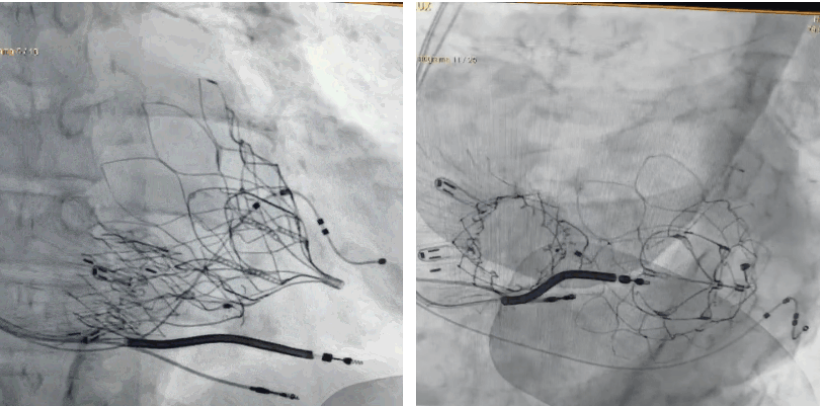

術(shù)后DSA顯示Lux-Valve Plus與Tendyne和ICD無相互影響

手術(shù)在全麻狀態(tài)下進行。術(shù)者采用經(jīng)右側(cè)頸靜脈入路的方式將輸送器送入患者心臟內(nèi),在TEE及DSA引導(dǎo)下調(diào)整輸送器頭端角度,使得輸送器與三尖瓣瓣環(huán)平面垂直。在輸送器進入右心室后釋放室間隔錨定裝置,而后釋放瓣葉夾持件(2個耳片結(jié)構(gòu))成垂直狀態(tài)。在TEE及DSA確定夾持件固定至三尖瓣葉根部且位于右室側(cè)后釋放人工瓣心房側(cè)盤片。隨后調(diào)整瓣膜同軸性以及室間隔錨定件位置(貼合室間隔),前推藏針管并固定,進而釋放室間隔錨定裝置,并再次確認瓣膜位置、穩(wěn)定性及同軸性,合攏輸送鞘后撤出輸送器,完成LuX-Valve Plus人工三尖瓣瓣膜的植入,僅殘余微量瓣周漏。且經(jīng)手術(shù)中心電生理團隊評估,病人的起搏器和ICD功能沒有受到影響。